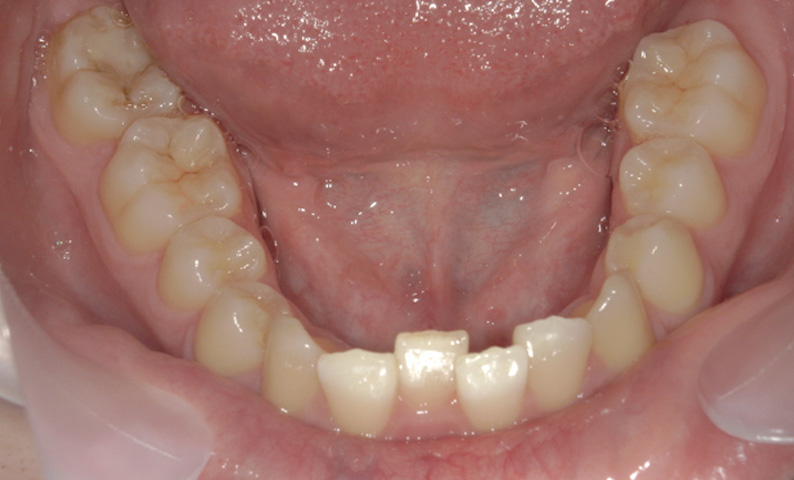

症例_008 「上下の前歯」症例

治療期間:13ヶ月金額:57万円+税40代女性捻転歯前歯のガタガタ

Before | After |

症例_008

治療リスク:後戻りの可能性